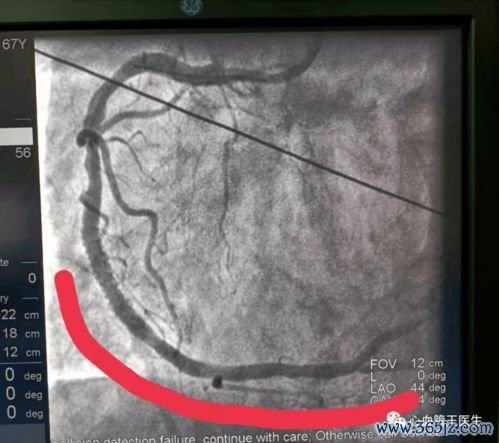

心肌梗死(心梗)经皮冠状动脉介入治疗(PCI,俗称“心脏支架手术”)后,患者迎来了生命的新起点。支架的植入并非一劳永逸,术后管理,尤其是饮食管理,是决定康复质量、预防二次心梗及心血管事件复发的核心环节。科学的饮食如同为脆弱的心脏构筑一道坚固的“营养防线”,通过控制危险因素、减轻心脏负荷、促进血管修复,从根本上降低复发风险。本文旨在提供一份详尽、可操作的术后防复发饮食指南,为患者及家属指明餐桌上的健康方向。